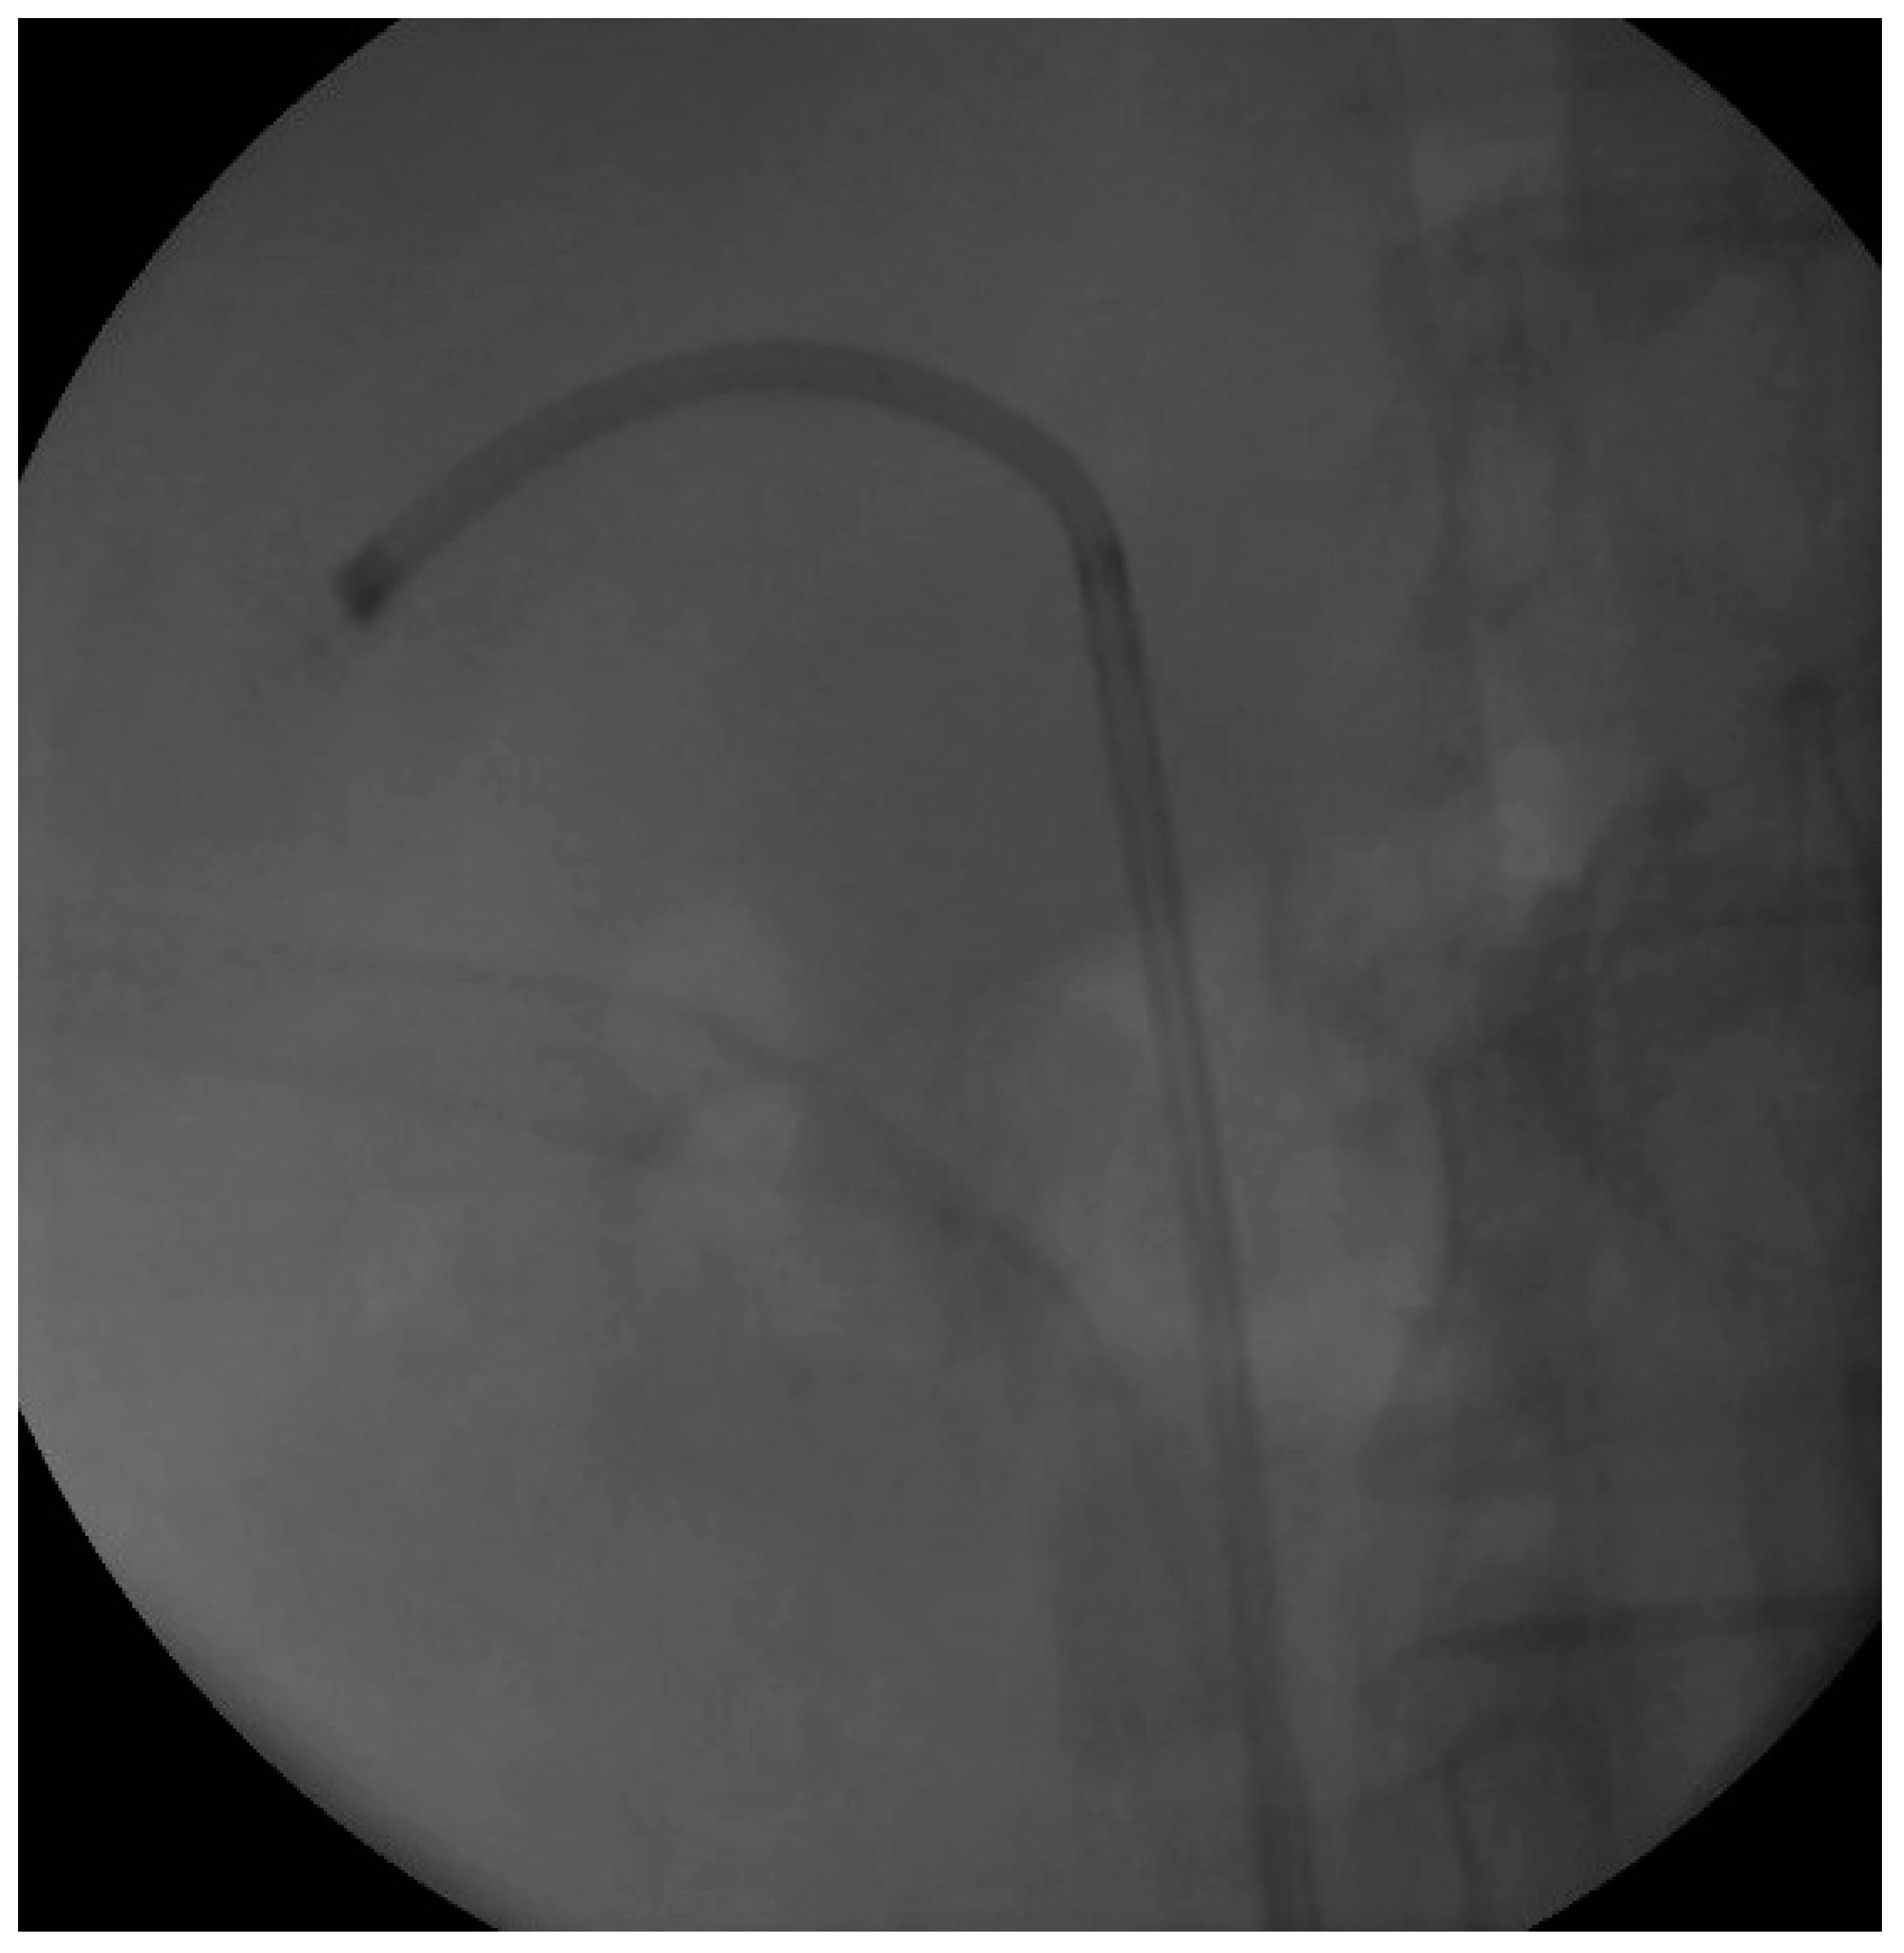

We proceeded with our standardized protocol of RIRS. Under general anesthesia, the patient was placed in the lithotomy position. At first, we performed a cystoscopy of the bladder. We found the right ureteral orifice and placed an ureteral catheter. Via the catheter, contrast agent was infused and, under fluoroscopy, the renal collecting system and the calculi was detected (Figure 1). The insertion of the guidewire followed, an ureteral access sheath was placed and through it we reached the kidney with a flexible ureteroscope of 8.6 French. The stones were found in the upper calyx and in the pelvis (Figure 2) so we began lithotripsy using holmium laser, checking throughout the whole procedure with fluoroscopy. In the meantime, the contrast agent was almost eliminated from the pelvicalyceal system and the stones were efficiently exported. Although we could not see any other calculi in the system, in the fluoroscopy there seemed to be one more (Figure 3). Therefore, we continued our endoscopy in order to find it. We came up to a small aperture in the spot that was indicated to us by the fluoroscopy, so we diagnosed an infundibulum stenosis and thought that the calculi would be within the calyx. The ureteroscope could not be inserted due to the stenosis, so we used the laser to widen the aperture. When the bore was opened and the access to the calyx was provided (Figure 4) we still could not found any calculi. In the fluoroscopy the sign has disappeared (Figure 5) so we understood that the contrast agent was entrapped in the calyx mimicking a stone in the fluoroscopy. The patient was stone free. We placed a double-J stent according to our protocol and the operation has ended. The patient the next day was free to leave the hospital without any complications, according to Clavien–Dildo system.

Figure 3. Fluoroscopy Image at the end of the lithotripsy.

Figure 4. The calyx after the widening of the infundibulum.